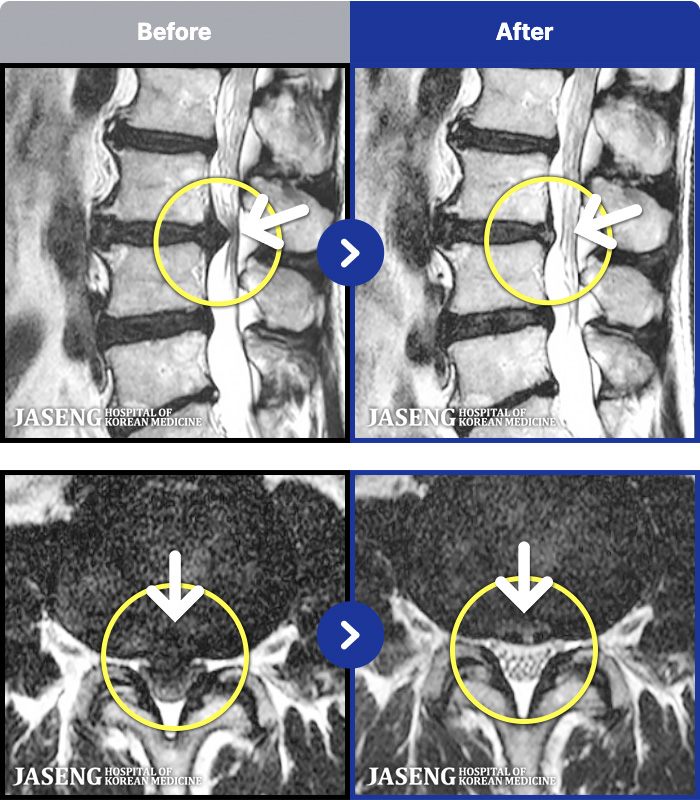

1,286 MRI ũ ʸ Ȯϼ.

[ϻ] 24.07.25~25.08.01